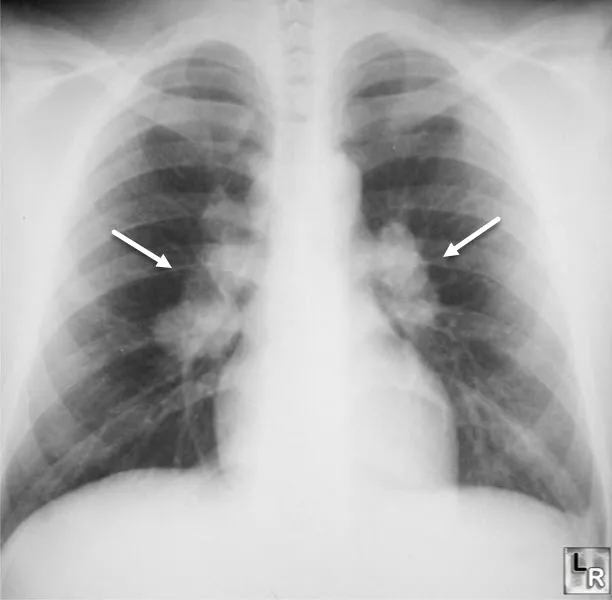

Granulomatous ILD - Lumpy, Bumpy Lungs

Sarcoidosis: Multisystem disease with non-caseating granulomas.

- Features: Bilateral hilar lymphadenopathy, ↑ serum ACE, hypercalcemia.